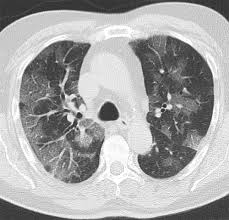

Black Hole In The Lung Bone Marrow Transplantation

Black Hole In The Lung Bone Marrow Transplantation from media.springernature.com